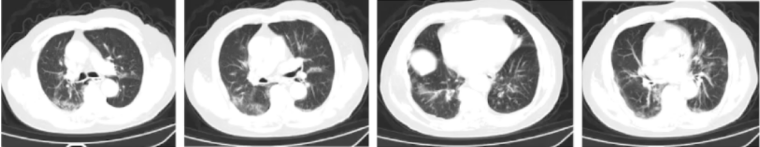

患者鼻导管吸氧2 L/min,2023年3月7日复查血气分析,PaO10.1 kPa(75.8 mmHg),SpO2能维持在95%以上。3月13日再次复查胸部CT,可见肺部间质性病变较前进一步吸收(图5)

图5  复查胸部CT(2023-03-13)